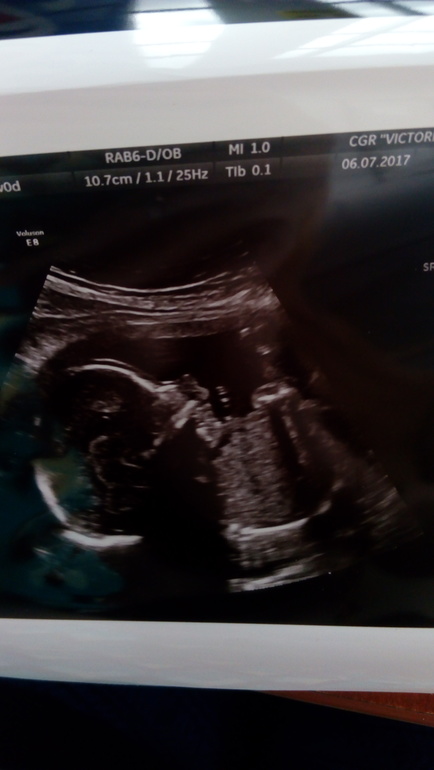

20 недель, экватор ))

Итак, что мы на сегодня имеем 😊

20 недель ровно, половина пути за спиной ✊

Ттт , все отличненько, девулька здоровенькая, растет и развивается😘😘😘

Ее вес уже 370 грамм;